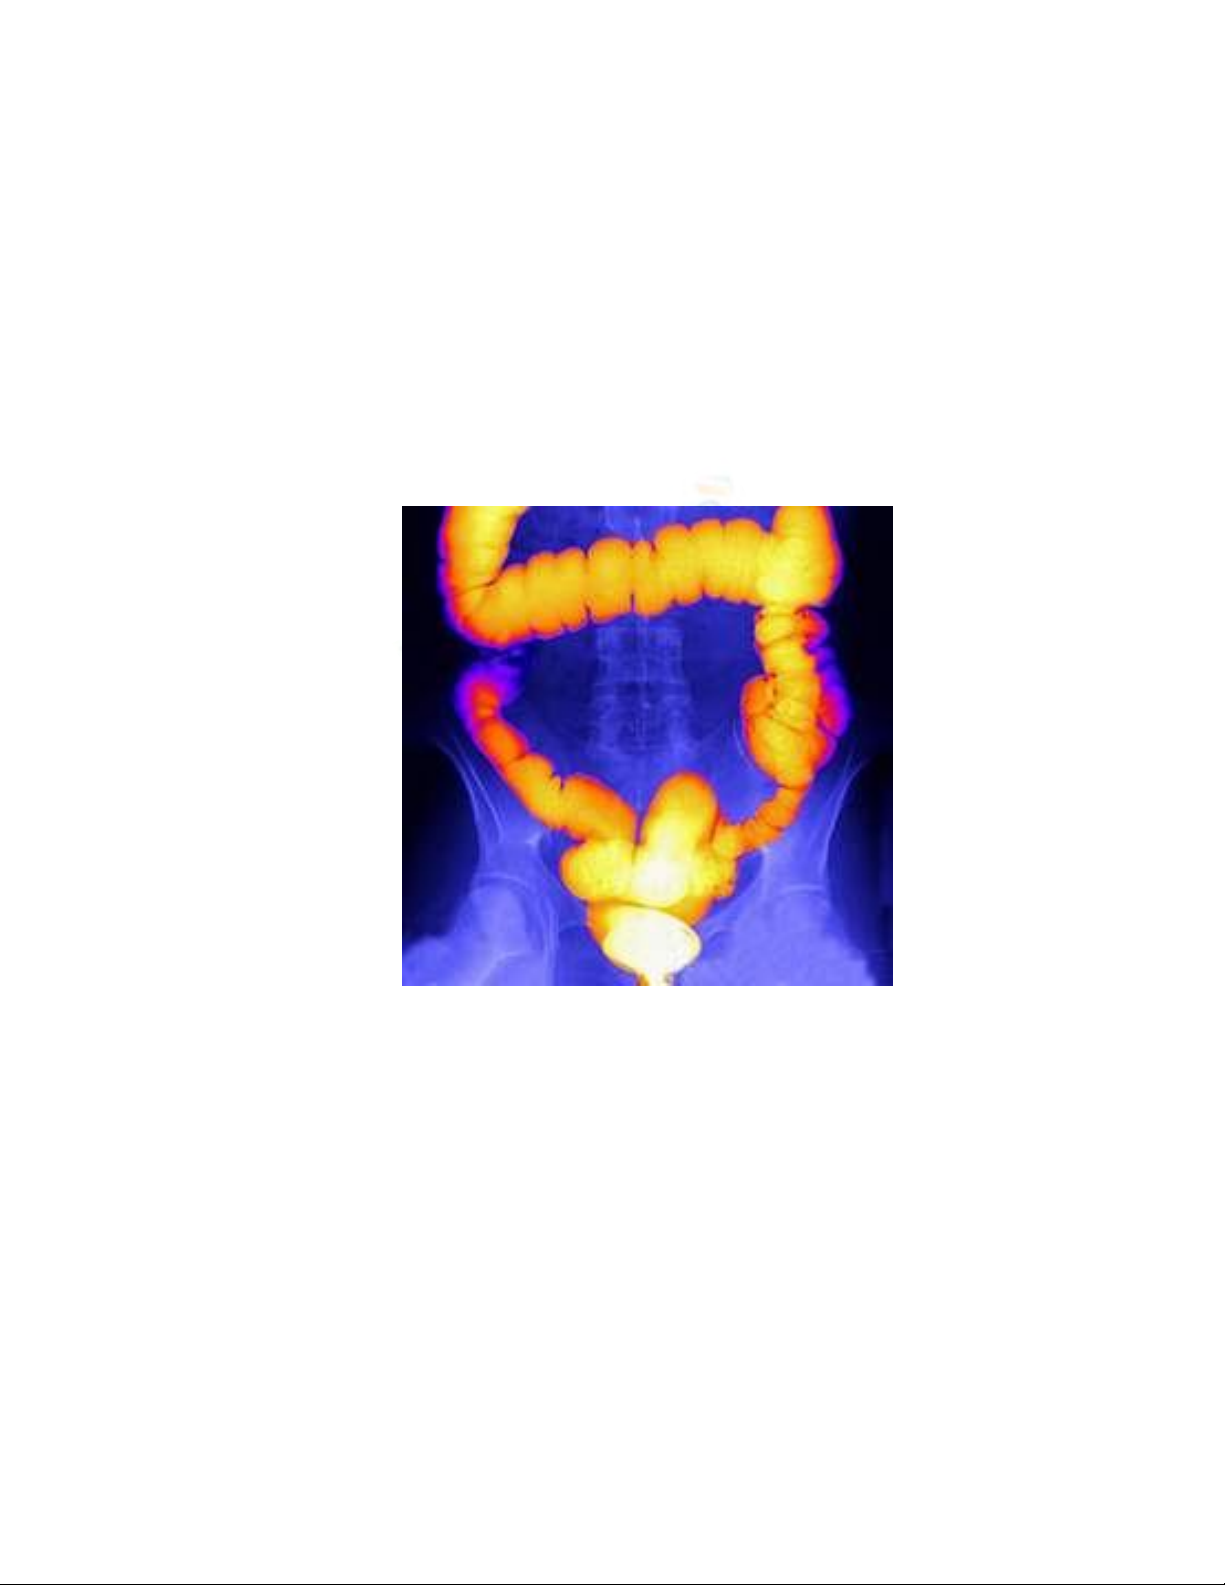

Hình ảnh trưc tràng trên phim có thuốc cản quang.